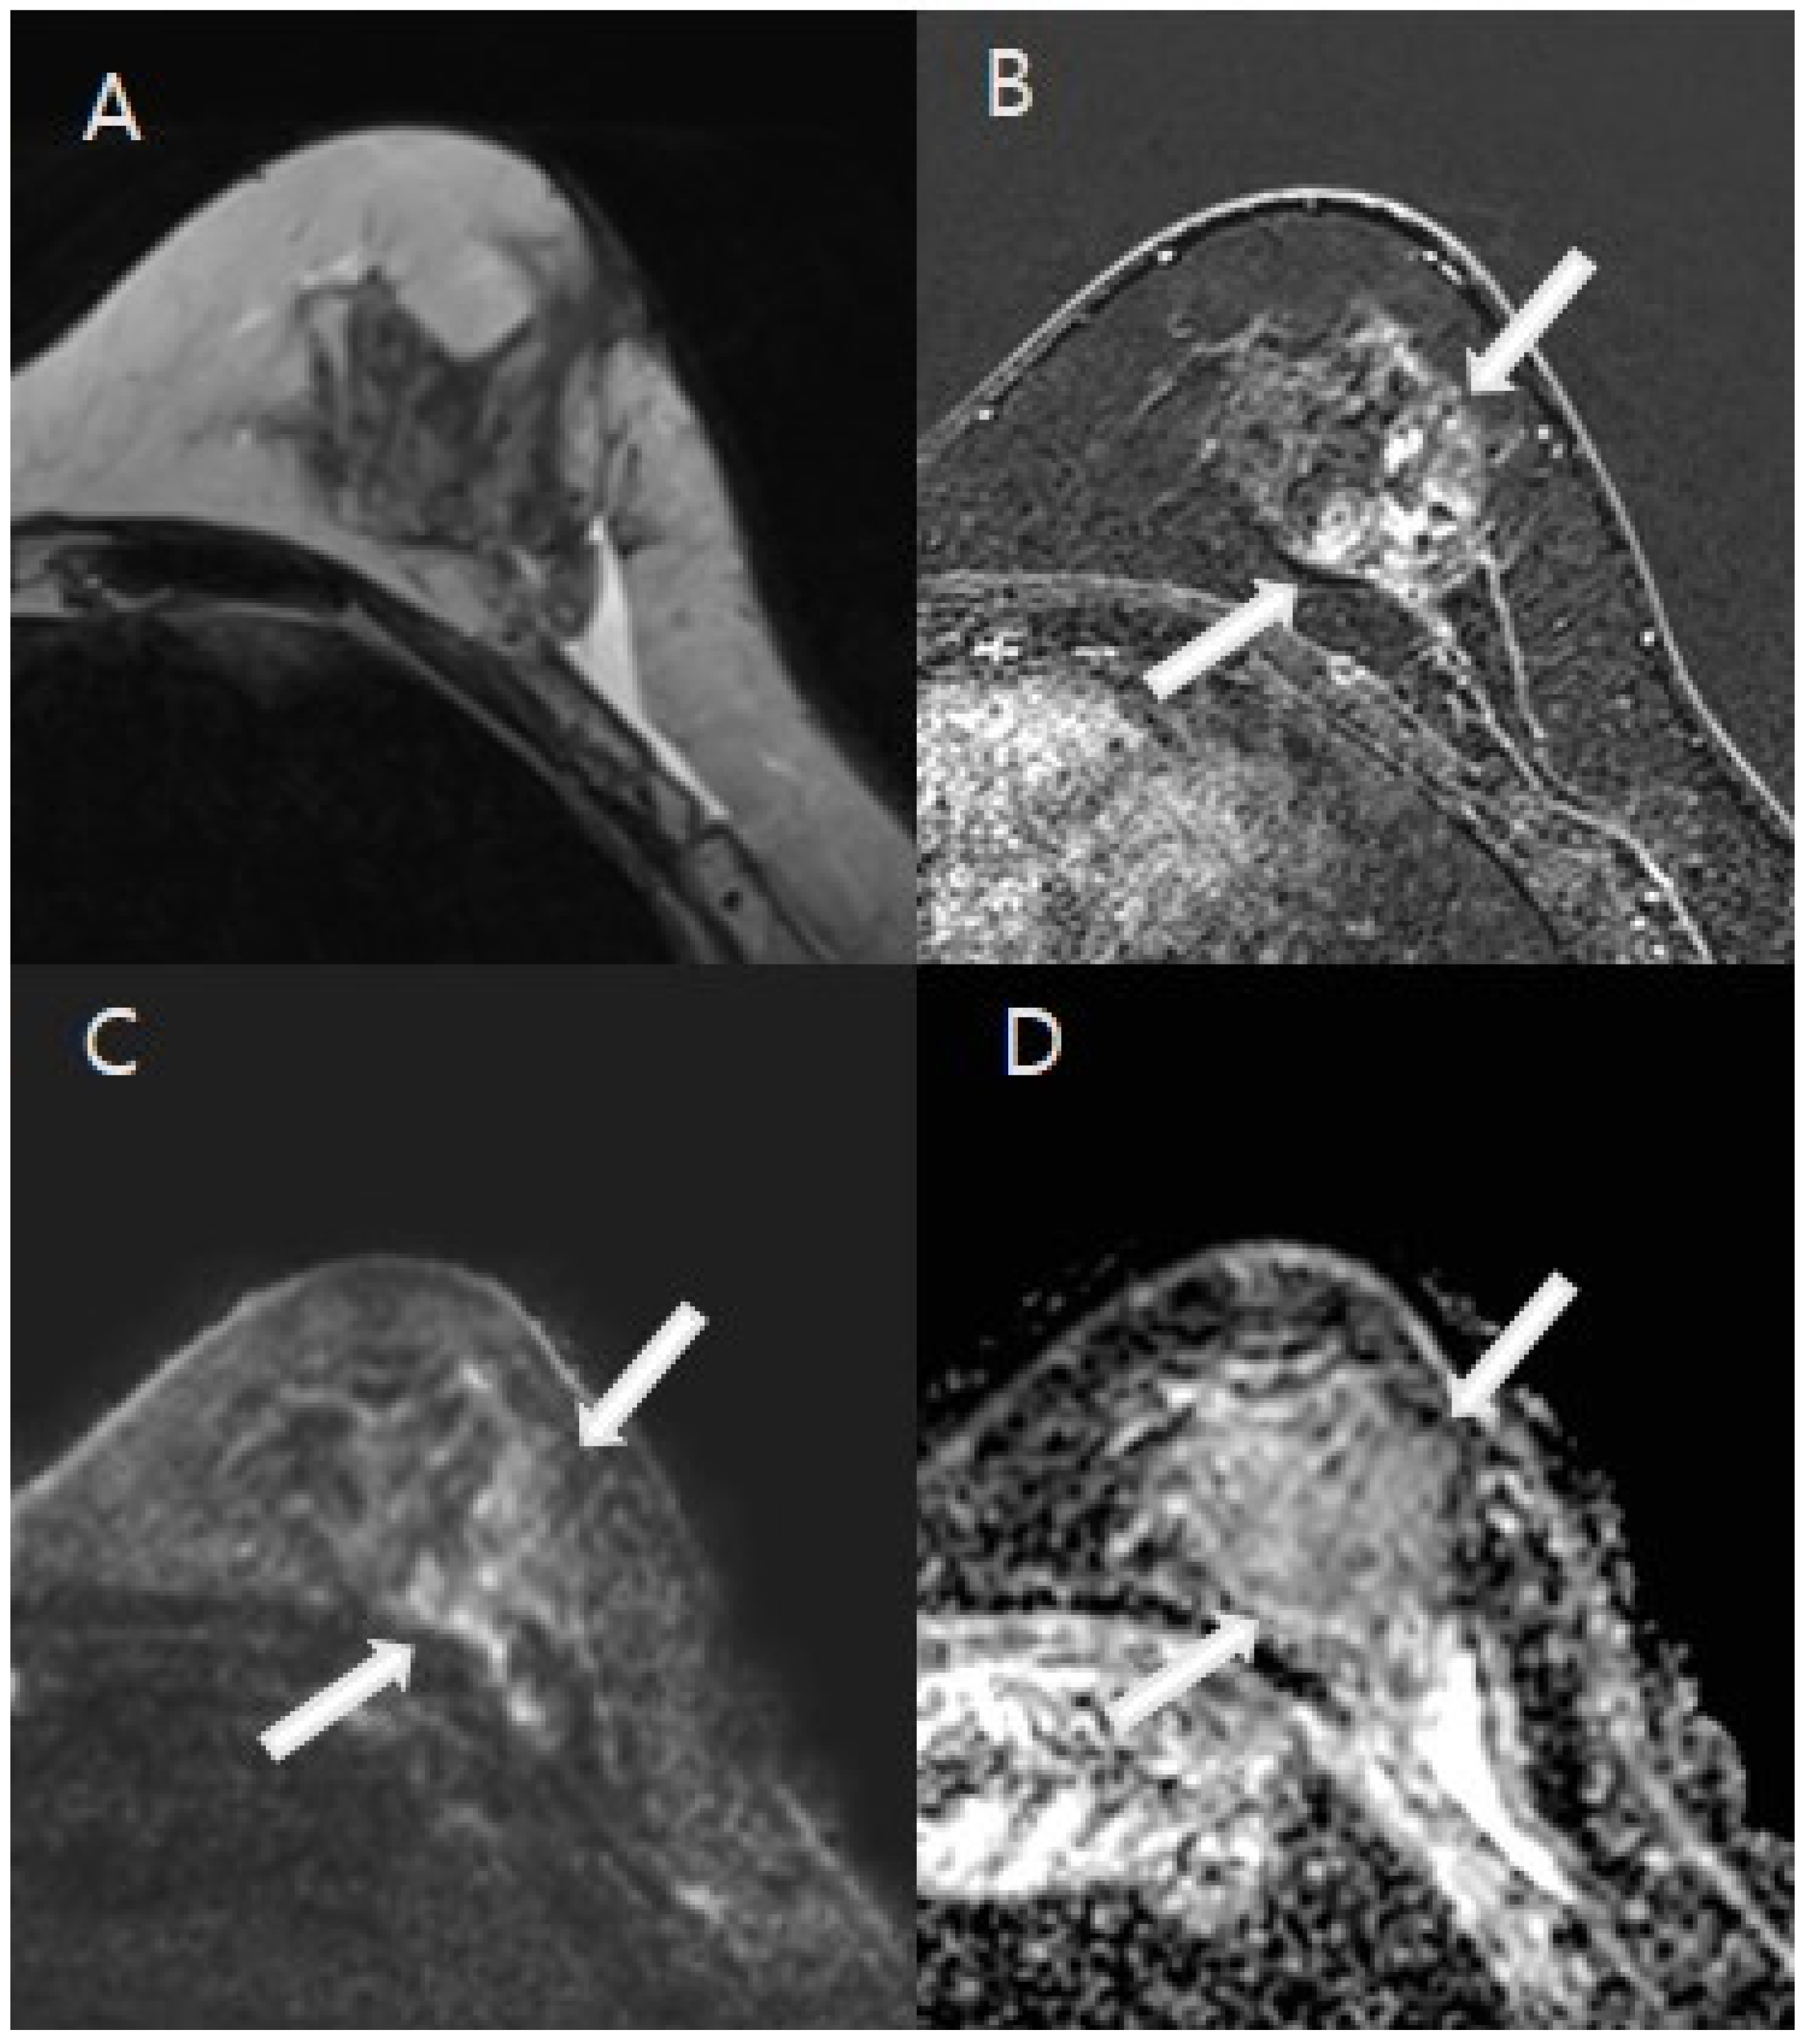

3.2. Image Analysis Results

3.3. The Diagnostic Performance of the Imaging Modalities